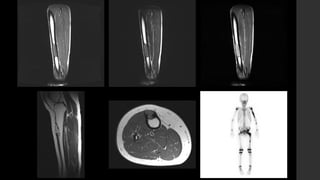

Tumor de Células Gigantes.

• IRM 

 T1 

 Componente sólido con señal intermedia a baja.

 Periferia con señal baja.

 T1+C 

 Realce de los componentes sólidos (lo distingue del quiste óseo aneurismático).

 Puede mostrar realce en la médula ósea adyacente.

 T2 

 Señal alta heterogénea con áreas de señal baja (debido a hemosiderina y fibrosis).

 Si hay componente quístico óseo aneurismático puede mostrar niveles líquido – líquido.

 Si hay señal alta adyacente a la médula ósea puede deberse a edema.